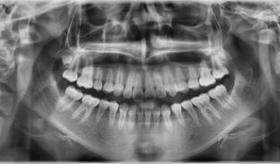

Combinaciones específicas de la forma del diente y la ubicación del diente en el pulido, tienen una influencia en la carga mecánica sobre la articulación temporomandibular.